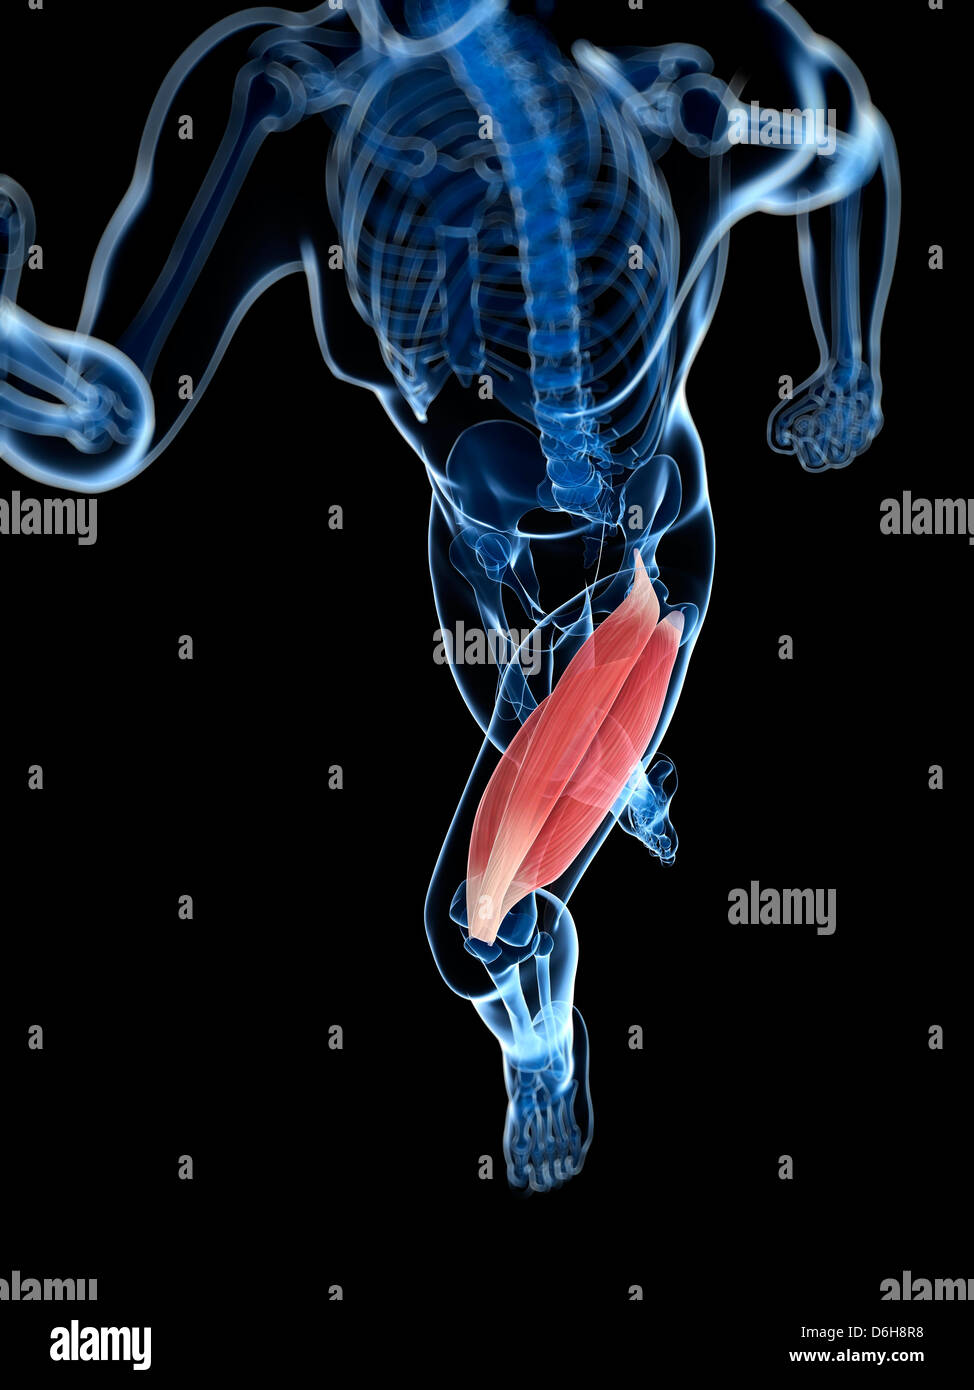

La cuisse, artwork Banque D'Imageshttps://www.alamyimages.fr/image-license-details/?v=1https://www.alamyimages.fr/photo-image-la-cuisse-artwork-55699139.html

La cuisse, artwork Banque D'Imageshttps://www.alamyimages.fr/image-license-details/?v=1https://www.alamyimages.fr/photo-image-la-cuisse-artwork-55699139.htmlRFD6H8PY–La cuisse, artwork

La cuisse, artwork Banque D'Imageshttps://www.alamyimages.fr/image-license-details/?v=1https://www.alamyimages.fr/photo-image-la-cuisse-artwork-55699143.html

La cuisse, artwork Banque D'Imageshttps://www.alamyimages.fr/image-license-details/?v=1https://www.alamyimages.fr/photo-image-la-cuisse-artwork-55699143.htmlRFD6H8R3–La cuisse, artwork

La cuisse, artwork Banque D'Imageshttps://www.alamyimages.fr/image-license-details/?v=1https://www.alamyimages.fr/photo-image-la-cuisse-artwork-55699138.html

La cuisse, artwork Banque D'Imageshttps://www.alamyimages.fr/image-license-details/?v=1https://www.alamyimages.fr/photo-image-la-cuisse-artwork-55699138.htmlRFD6H8PX–La cuisse, artwork

La cuisse, artwork Banque D'Imageshttps://www.alamyimages.fr/image-license-details/?v=1https://www.alamyimages.fr/photo-image-la-cuisse-artwork-55699148.html

La cuisse, artwork Banque D'Imageshttps://www.alamyimages.fr/image-license-details/?v=1https://www.alamyimages.fr/photo-image-la-cuisse-artwork-55699148.htmlRFD6H8R8–La cuisse, artwork